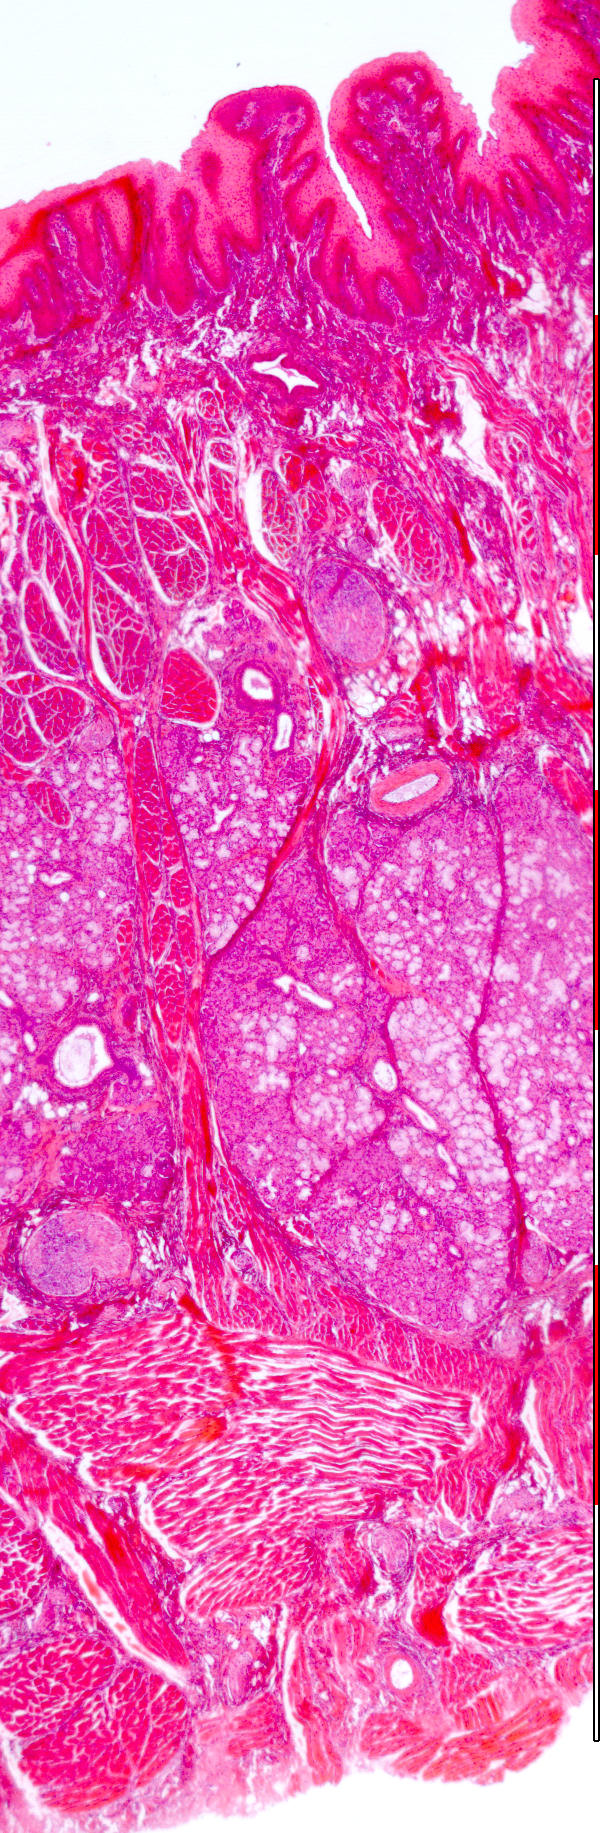

Tongue

© mei 2007 marius loots